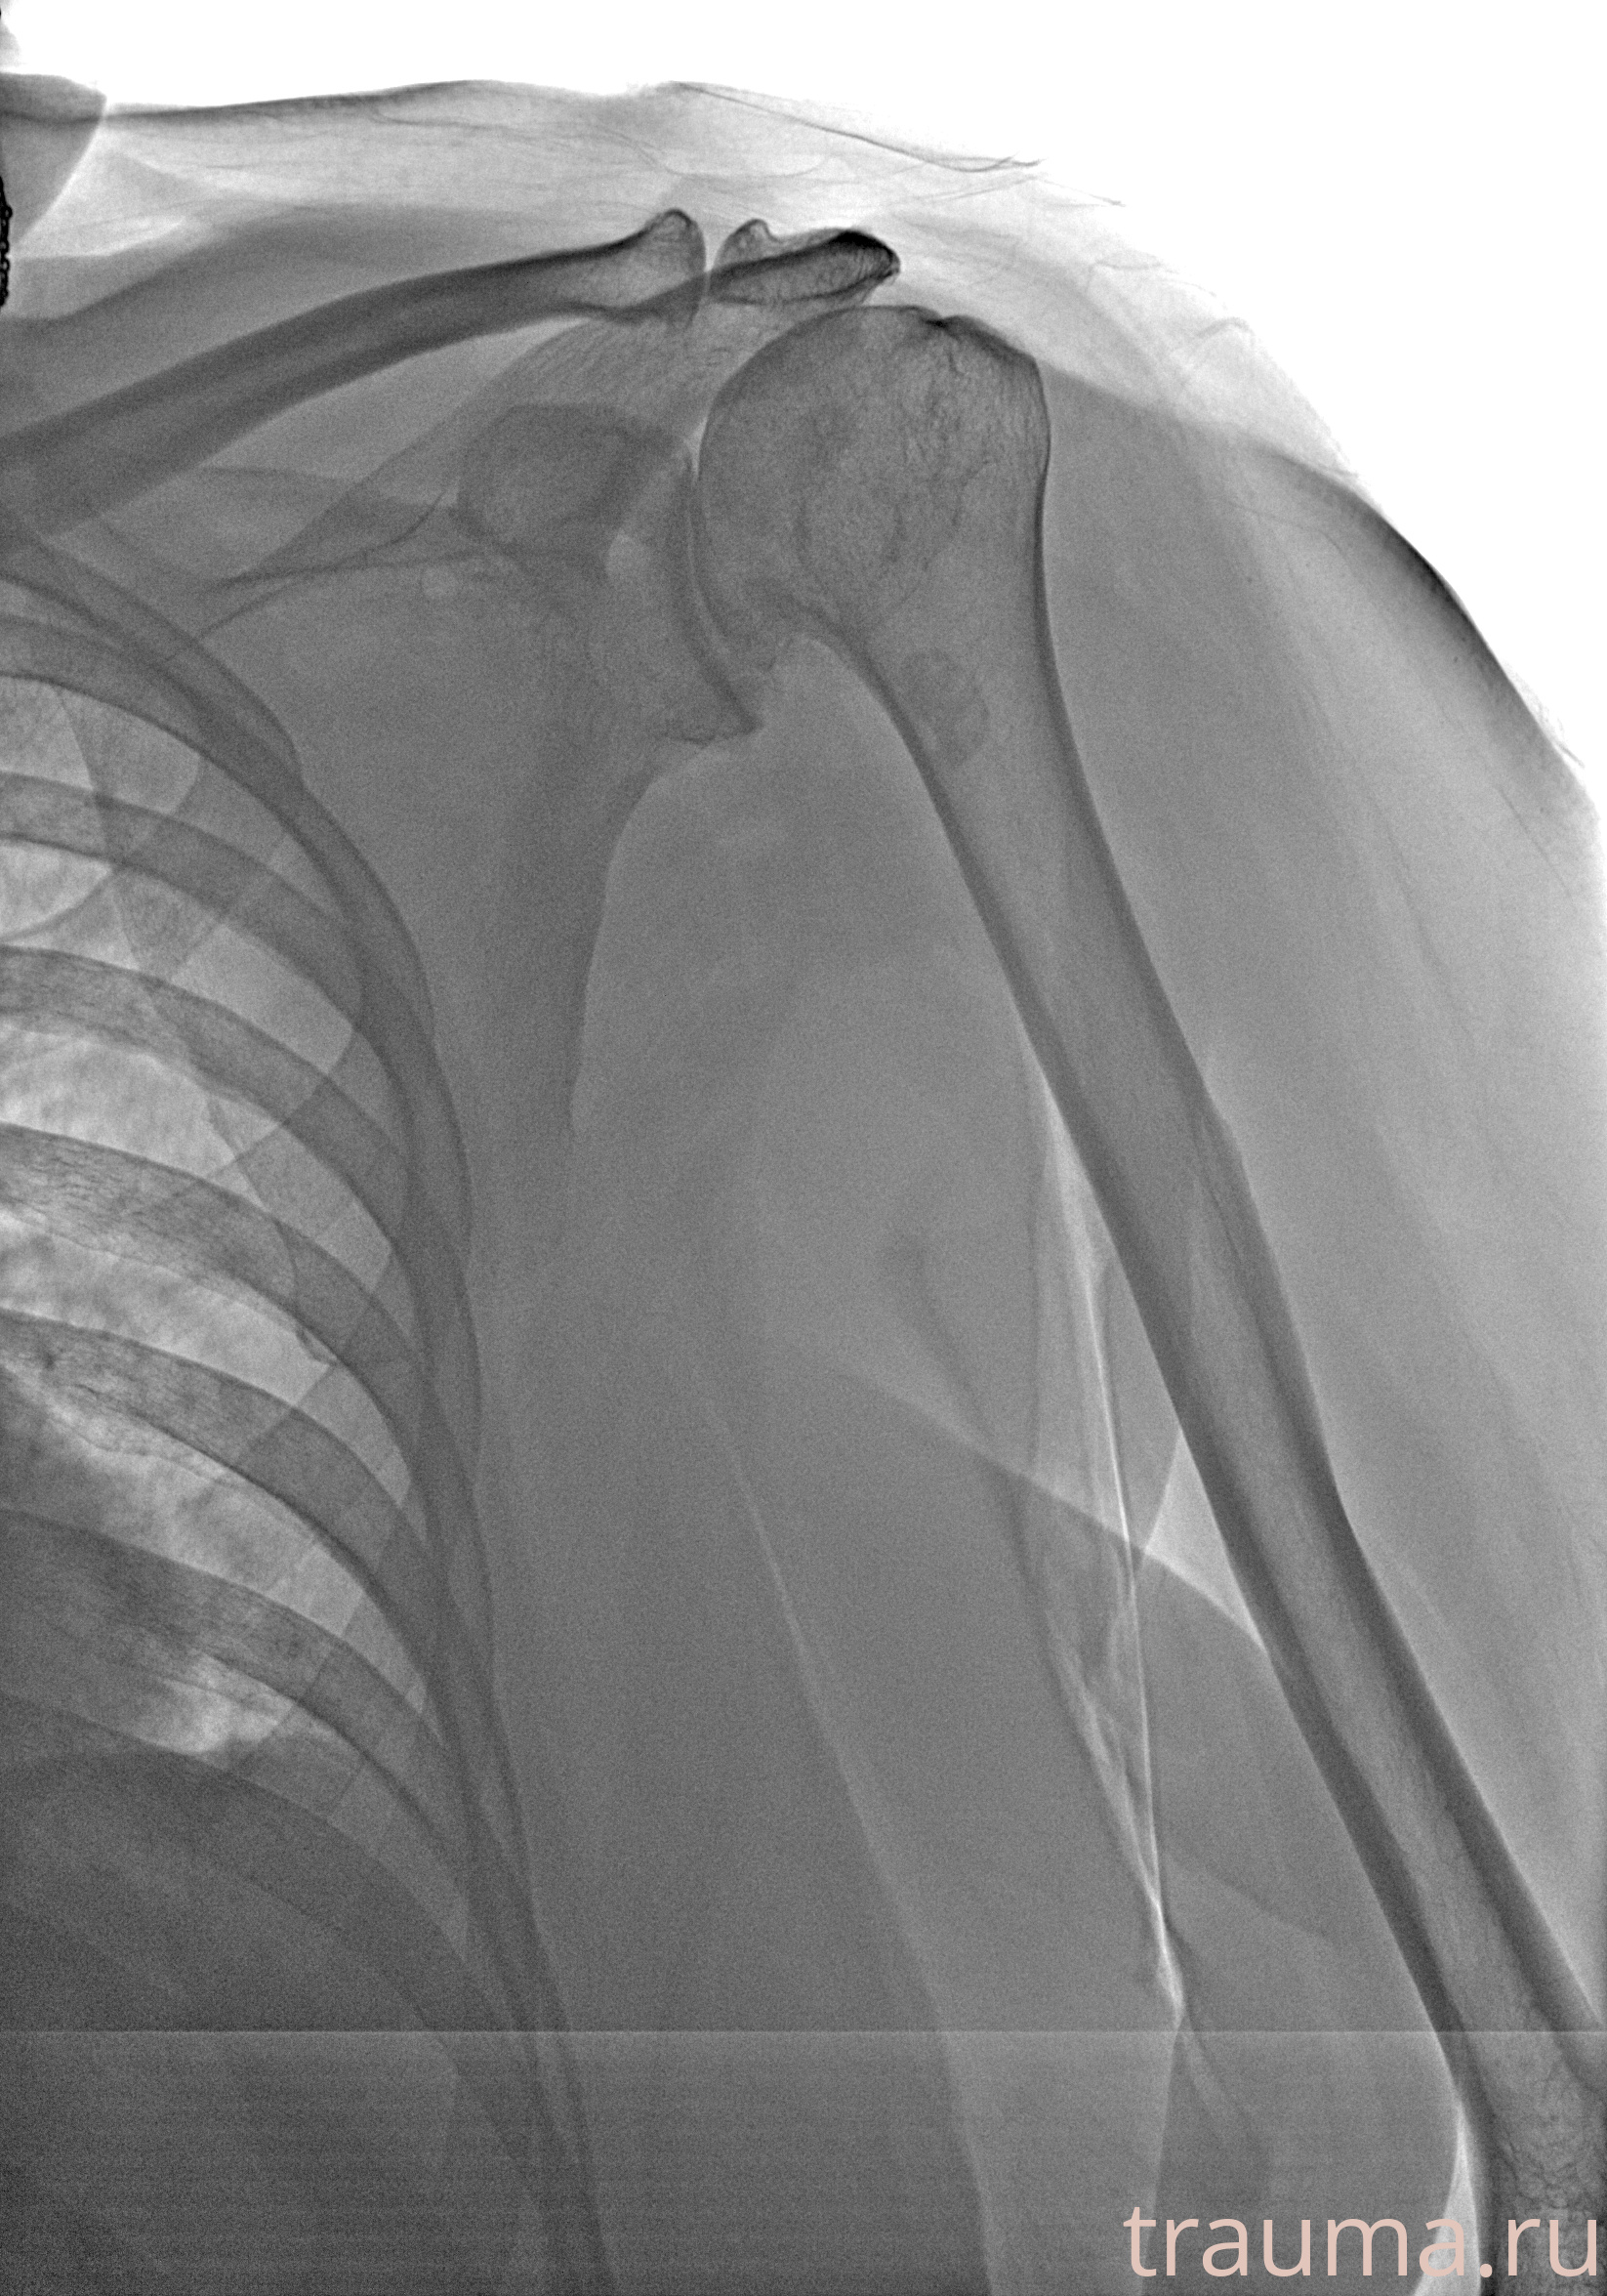

Рентгенограммы

Рентген на дому: по вашему адресу приезжает врач-рентгенолог, травматолог-ортопед с мобильным рентгеновским аппаратом, проводит диагностику травмы или заболевания, делает необходимые рентгенограммы, дает рекомендации по дальнейшему лечению. Получить качественные снимки в домашних условиях возможно благодаря уникальной методике, разработанной МосРентген Центром для института  Склифосовского